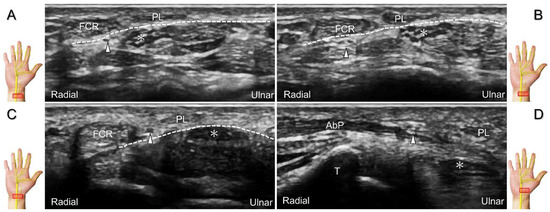

Scanning Technique

The transducer is first placed in the axial plane over the distal forearm with the forearm supinated to locate the median nerve between the flexor digitorum superficialis and profundus muscles (Figure 7A). Moving the transducer distally, the palmar cutaneous branch of the median nerve, shown as a single hypoechoic fascicle, emerges from the radial aspect of the median nerve (Figure 7B) [32]. The nerve then penetrates the antebrachial fascia and runs on the ulnar aspect of the flexor carpi radialis tendon (Figure 7C). Eventually, the nerve can be identified superficial to the abductor pollicis brevis muscle (Figure 7D).

Figure 7. Sonographic imaging of the palmar cutaneous branch of the median nerve (A) shows its emerging from the radial aspect of the median nerve (B), penetrating the antebrachial fascia (C), and arriving at the superficial site of the abductor pollicis brevis muscle (D). Asterisk: median nerve; arrowhead: palmar cutaneous branch of the median nerve; dashed line, antebrachial fascia; FCR: flexor carpi radialis tendon; T: trapezium; PL: palmaris longus tendon; AbP: abductor pollicis brevis muscle.